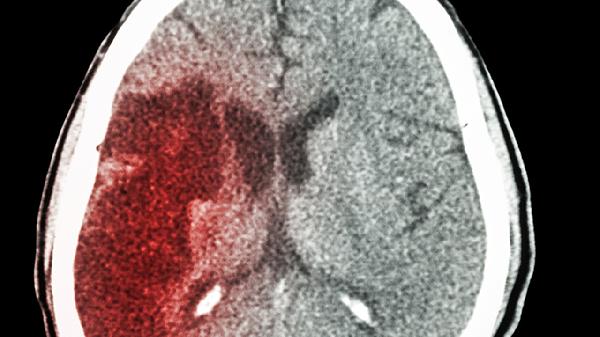

脑出血一侧身体不能动怎么回事

脑出血一侧身体不能动可能由出血部位压迫运动神经、脑水肿、神经传导通路受损、脑组织缺血坏死、继发脑疝等原因引起,可通过药物治疗、手术治疗、康复训练等方式改善。脑出血属于急症,需立即就医。

脑出血后血肿直接压迫运动神经传导通路,导致对侧肢体运动功能障碍。常见于基底节区出血,患者可能出现偏瘫伴言语不清。需通过头颅CT明确出血量,出血量超过30毫升时需行开颅血肿清除术或微创穿刺引流术,可遵医嘱使用甘露醇注射液降低颅内压,配合神经节苷脂钠注射液营养神经。